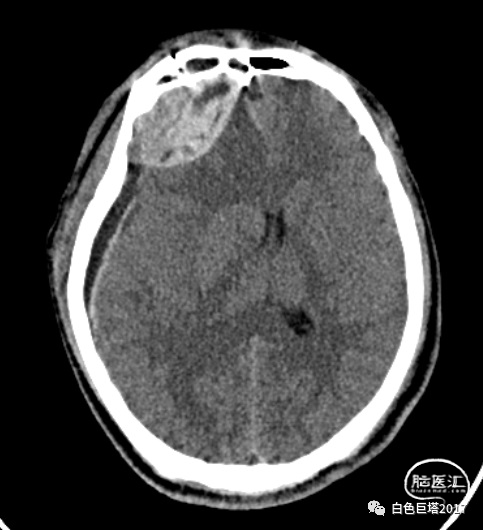

患者苏某,34岁男性,因“高处坠落致意识障碍1小时余”入院。患者自8米高处坠落,头面部着地,入院时头面创口、口腔、鼻腔流血不止,GCS E2V1M5为8分。很快出现血压下降至70/52mmHg、血氧下降85%。急诊气管插管,完善头颅、颈椎、胸腹部CT检查,提示颌面、颅底多发骨折、鼻腔积血,软组织挫裂伤,左颞颌关节脱位,牙齿缺失。额骨骨折、右额顶叶脑挫裂伤、蛛网膜下腔出血,颅内积气。颈椎间盘突出、颈椎退行性变、未见明显骨折。双侧1-2肋骨骨折,T5-7左侧横突骨折;双肺挫伤;左侧少量气胸。腹腔脏器未见明显损伤表现。

术后复查